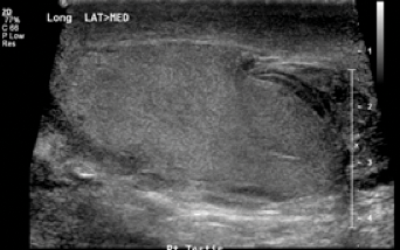

A 32-year-old male was kicked in the scrotum during a game of rugby. A clinical image and ultrasound of the testes is shown.

1. What is the diagnosis?

1. Rupture of testicular tunica albuginea.

2. Early surgical intervention for blunt trauma is associated with higher salvage rates (94% vs. 79%).

3. Scrotal trauma can be divided into blunt, penetrating and degloving injures. Severity of injury is classified by the American Association for Surgery and Trauma (AAST).

4. Surgical exploration involves evacuation of clots and haematoma. Necrotic tissue and tubules should be excised with closure of the tunica albuginea (with absorbable sutures).